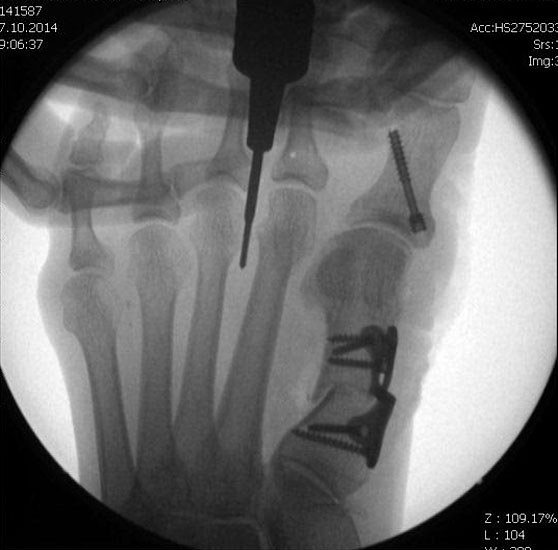

Jetzt erfolgt das Einbringen der Fräse im 45°-Winkel von distal dorsal nach proximal plantar. Auf steten Knochenkontakt mit der Kortikalis zur Vermeidung eines Weichteilinterponates sollte geachtet werden. In unserer Abteilung erfolgt vor Beginn der Osteotomie nun eine nochmalige Lagekontrolle der Fräse unter dem Bildwandler im dorsoplantaren Strahlengang. Eine zusätzliche laterale Aufnahme kann die Tiefe der eingebrachten Fräse in Bezug auf das zu osteomierende Metatarsale zeigen, ebenso ermöglicht sie eine Kontrolle des 45°-Winkels.

In einer rotatorischen Bewegung mit dem Drehpunkt im Bereich der Hautinzision erfolgt nun die Osteotomie zunächst - in Abhängigkeit von der zu operierenden Seite und der Rechts- oder Linkshändigkeit des Operateurs  - des medialen bzw. lateralen Kortex des Metatarsale, gefolgt von den plantaren Anteilen und anschliessend dem gegenseitigen Kortex. Am Ende der rotatorischen Bewegung befindet sich die Fräse, die am Anfang der Osteotomie noch parallel zum Metatarsaleschaft ausgerichtet war, im 90°-Winkel zu diesem.

Mit dem plantar unter dem Metatarsaleköpfchen aufliegenden Zeigefinger der Gegenhand kann die Vollständigkeit der  Osteotomie durch ein Nachlassen der Widerstandes unter dem Köpfchen palpiert werden. Falls nötig, kann dies auch durch Zug an der Zehe unter Bildwandler zusätzlich bestätigt werden. Das Metatarsaleköpfchen wandert durch die Osteotomie von allein um einige mm nach proximal und dorsal.  Eine zusätzliche manuelle Verkürzung des Metatarsale ist aus biomechanischen Gründen zu vermeiden.